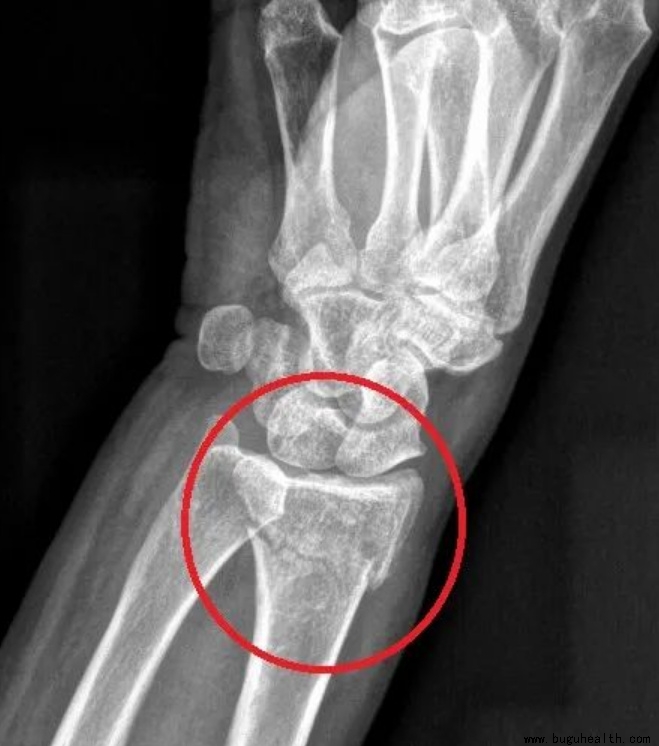

3. 桡骨远端骨折

属于手腕部的一种骨折!桡骨远端骨折是指距桡骨下端关节面3cm以内的骨折!跌倒手撑地时拇指那一侧会发生移位,严重的骨折会造成正中神经的卡压,从而引起手部肿胀、疼痛、皮下淤血。

未移位或者未涉及关节表面可保守治疗。如果桡骨远端骨折段的骨块保持对齐,没有明显的移位或错位,通常可以通过外部固定(如石膏固定或支具等外固定装置)来稳定,促使骨折部位愈合。

如果桡骨远端骨折没有涉及到关节表面,即关节面未受损,那么保守治疗的可能性也比较大。